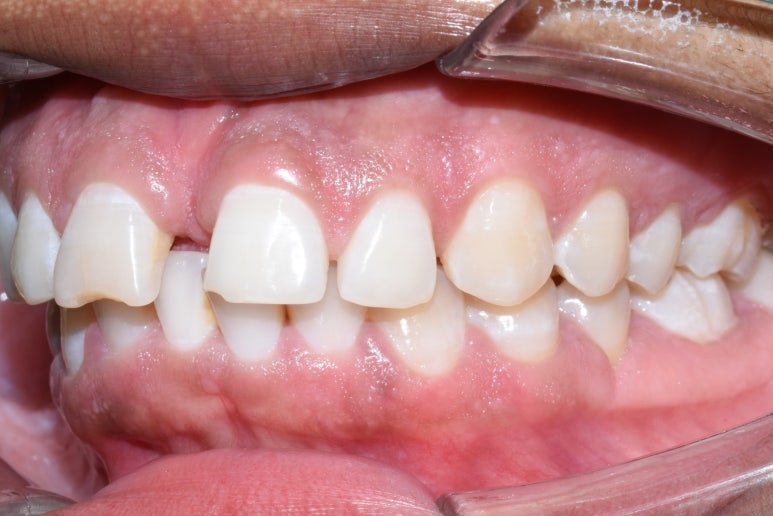

치료전 사진

이 외국인 환자분은 라미네이트를 생각하고 오셨는데요

워낙 앞니 사이 공간이 크고 치아가 뻐드러져 있어서

그냥 바로 라미네이트 치료를 하는 경우에 치아 사이 공간을 메우는 라미네이트가 너무 커져서

앞니 2개만 굉장히 커져 보일 수 있기 때문에

부분 교정을 하고, 라미네이트 4개를 하는 것으로 치료계획을 상담하였습니다.

위 사진과 같이 화살표 위아래로 전후 모습이 변화하였습니다.

치료 전 후

치료 전 후 얼마나 고르면서 치아 겉면 색도 하얗게 되었는지 비교가 되시죠?